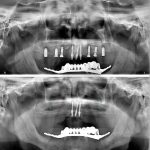

Tansel Hamza

Diş Estetiği ve İmplant (Bölüm 2)